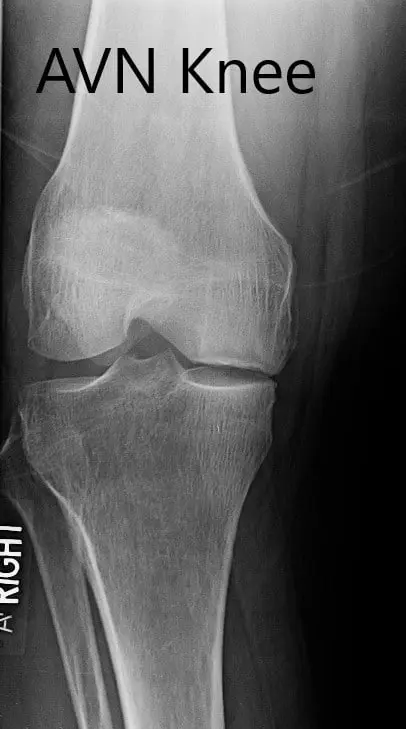

Preoperative X-ray of the right knee in anteroposterior and lateral views

Preoperative X-ray of the right knee in anteroposterior and lateral views - img 2

Preoperative X-ray of the right knee in anteroposterior and lateral views.